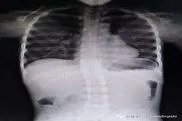

缺钙胸骨突出图片